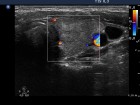

Ultrasonography: Both lobes were enlarged, moderately hypoechogenic, inhomogeneous and displayed increased vascularization.

Follow-up examinations (rows from 1st to 8th):

Corresponding sonographic images (row)

2. Note the relation between volume, echogenicity, vascularization and hormone levels.